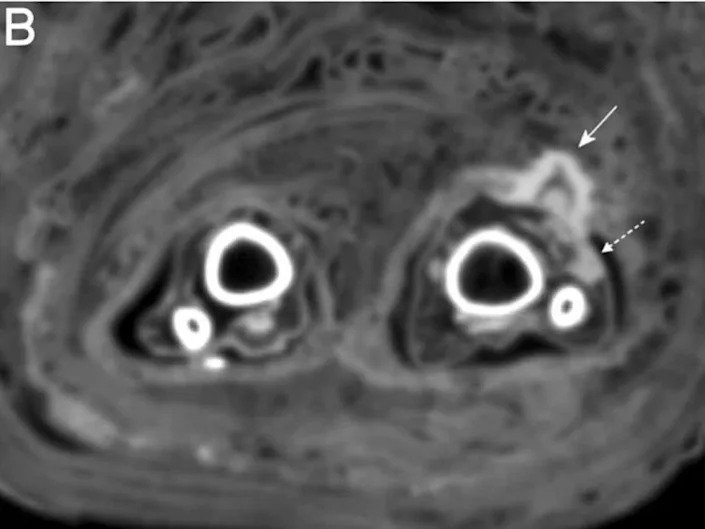

In this case, Zink said, the bandages were spotted while the scientists carried out routine CT scans of mummies, as can be seen in the scans below and annotated with the full-lined arrow.

The wound appeared to have been infected when she died, as the scans showed signs of “pus,” Zink said. These signs of infection are marked by the dotted arrows in the scans below.